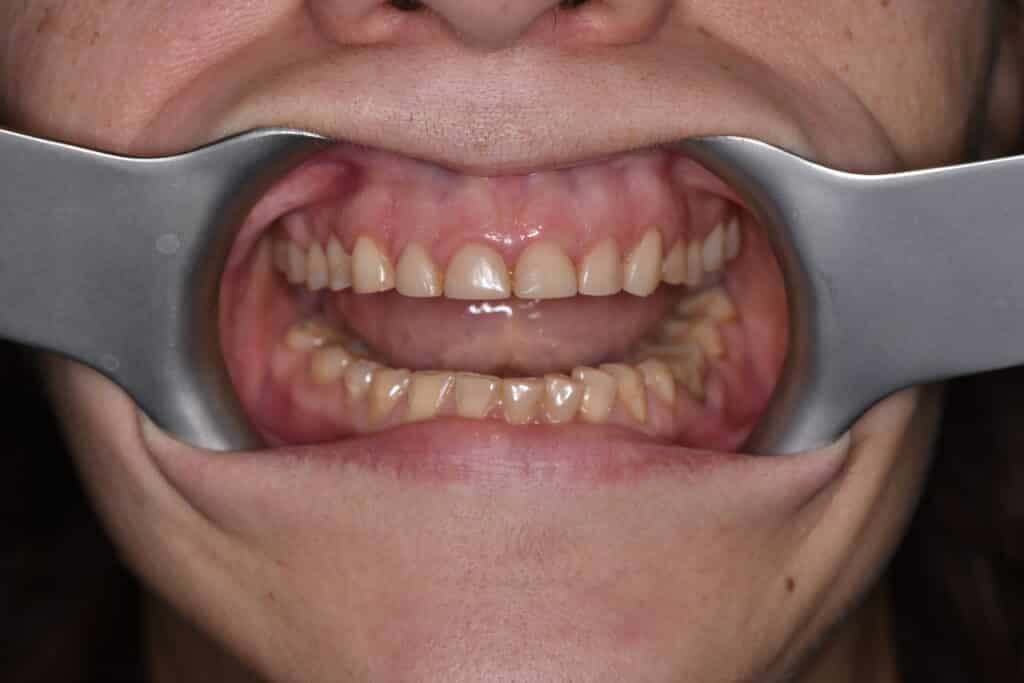

Die 38-jährige Patientin der Praxis Dr. Marius Bancila in München beklagte die unbefriedigende Ästhetik ihres Lächelns aufgrund der über die Jahre kurz gewor-denen, stark abradierten Zähne (Abb. 1).

Die Knirscherschiene, die sie zum Schutz

der Zahnsubstanz erhalten hatte, hatte sie kaum getragen. In der aktuellen Situation hatte die Patientin keine Schmerzen, war aber mit dem Erscheinungsbild ihres Lächelns sehr unzufrieden. Ihre allgemeine Anamnese war unauffällig. Der klinische Befund bestätigte, dass die Zähne im Ober- und Unterkiefer, besonders die Frontzähne des Oberkiefers, von starken Abrasionen betroffen waren. Darüber hinaus ergab der klinische Befund bei inkomplettem Zahndurchbruch und ske-lettaler Klasse Il zusätzlich Verfärbungen der Zahnsubstanz und Gingiva-Rezessio-nen (Abb. 2 und 3).